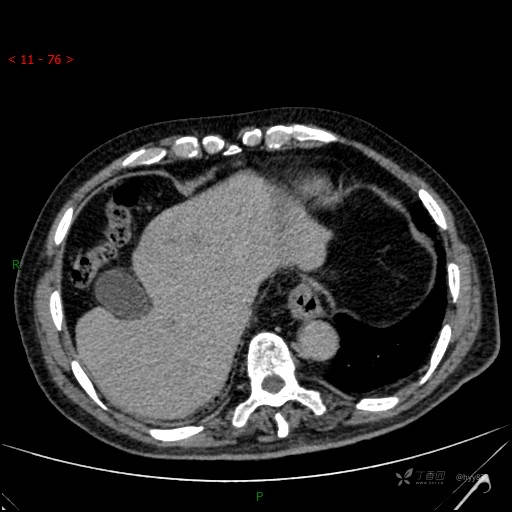

肝脏CT平扫

延迟期

img

肝脓肿 (73)